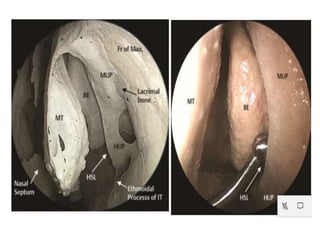

AGGER NASI CELL

It is present Anterior, lateral, and inferior to the

frontal recess .

It is aerated and represents the most anterior

ethmoid air cell, usually lying deep to the lacrimal

bone.

It usually borders the primary ostium or floor of

the frontal sinus.

its size may directly influence the patency of the

frontal recess and the anterior middle meatus.

Landmarks in FESS

Middle turbinate

Uncinate Process

Bulla Ethmoidalis